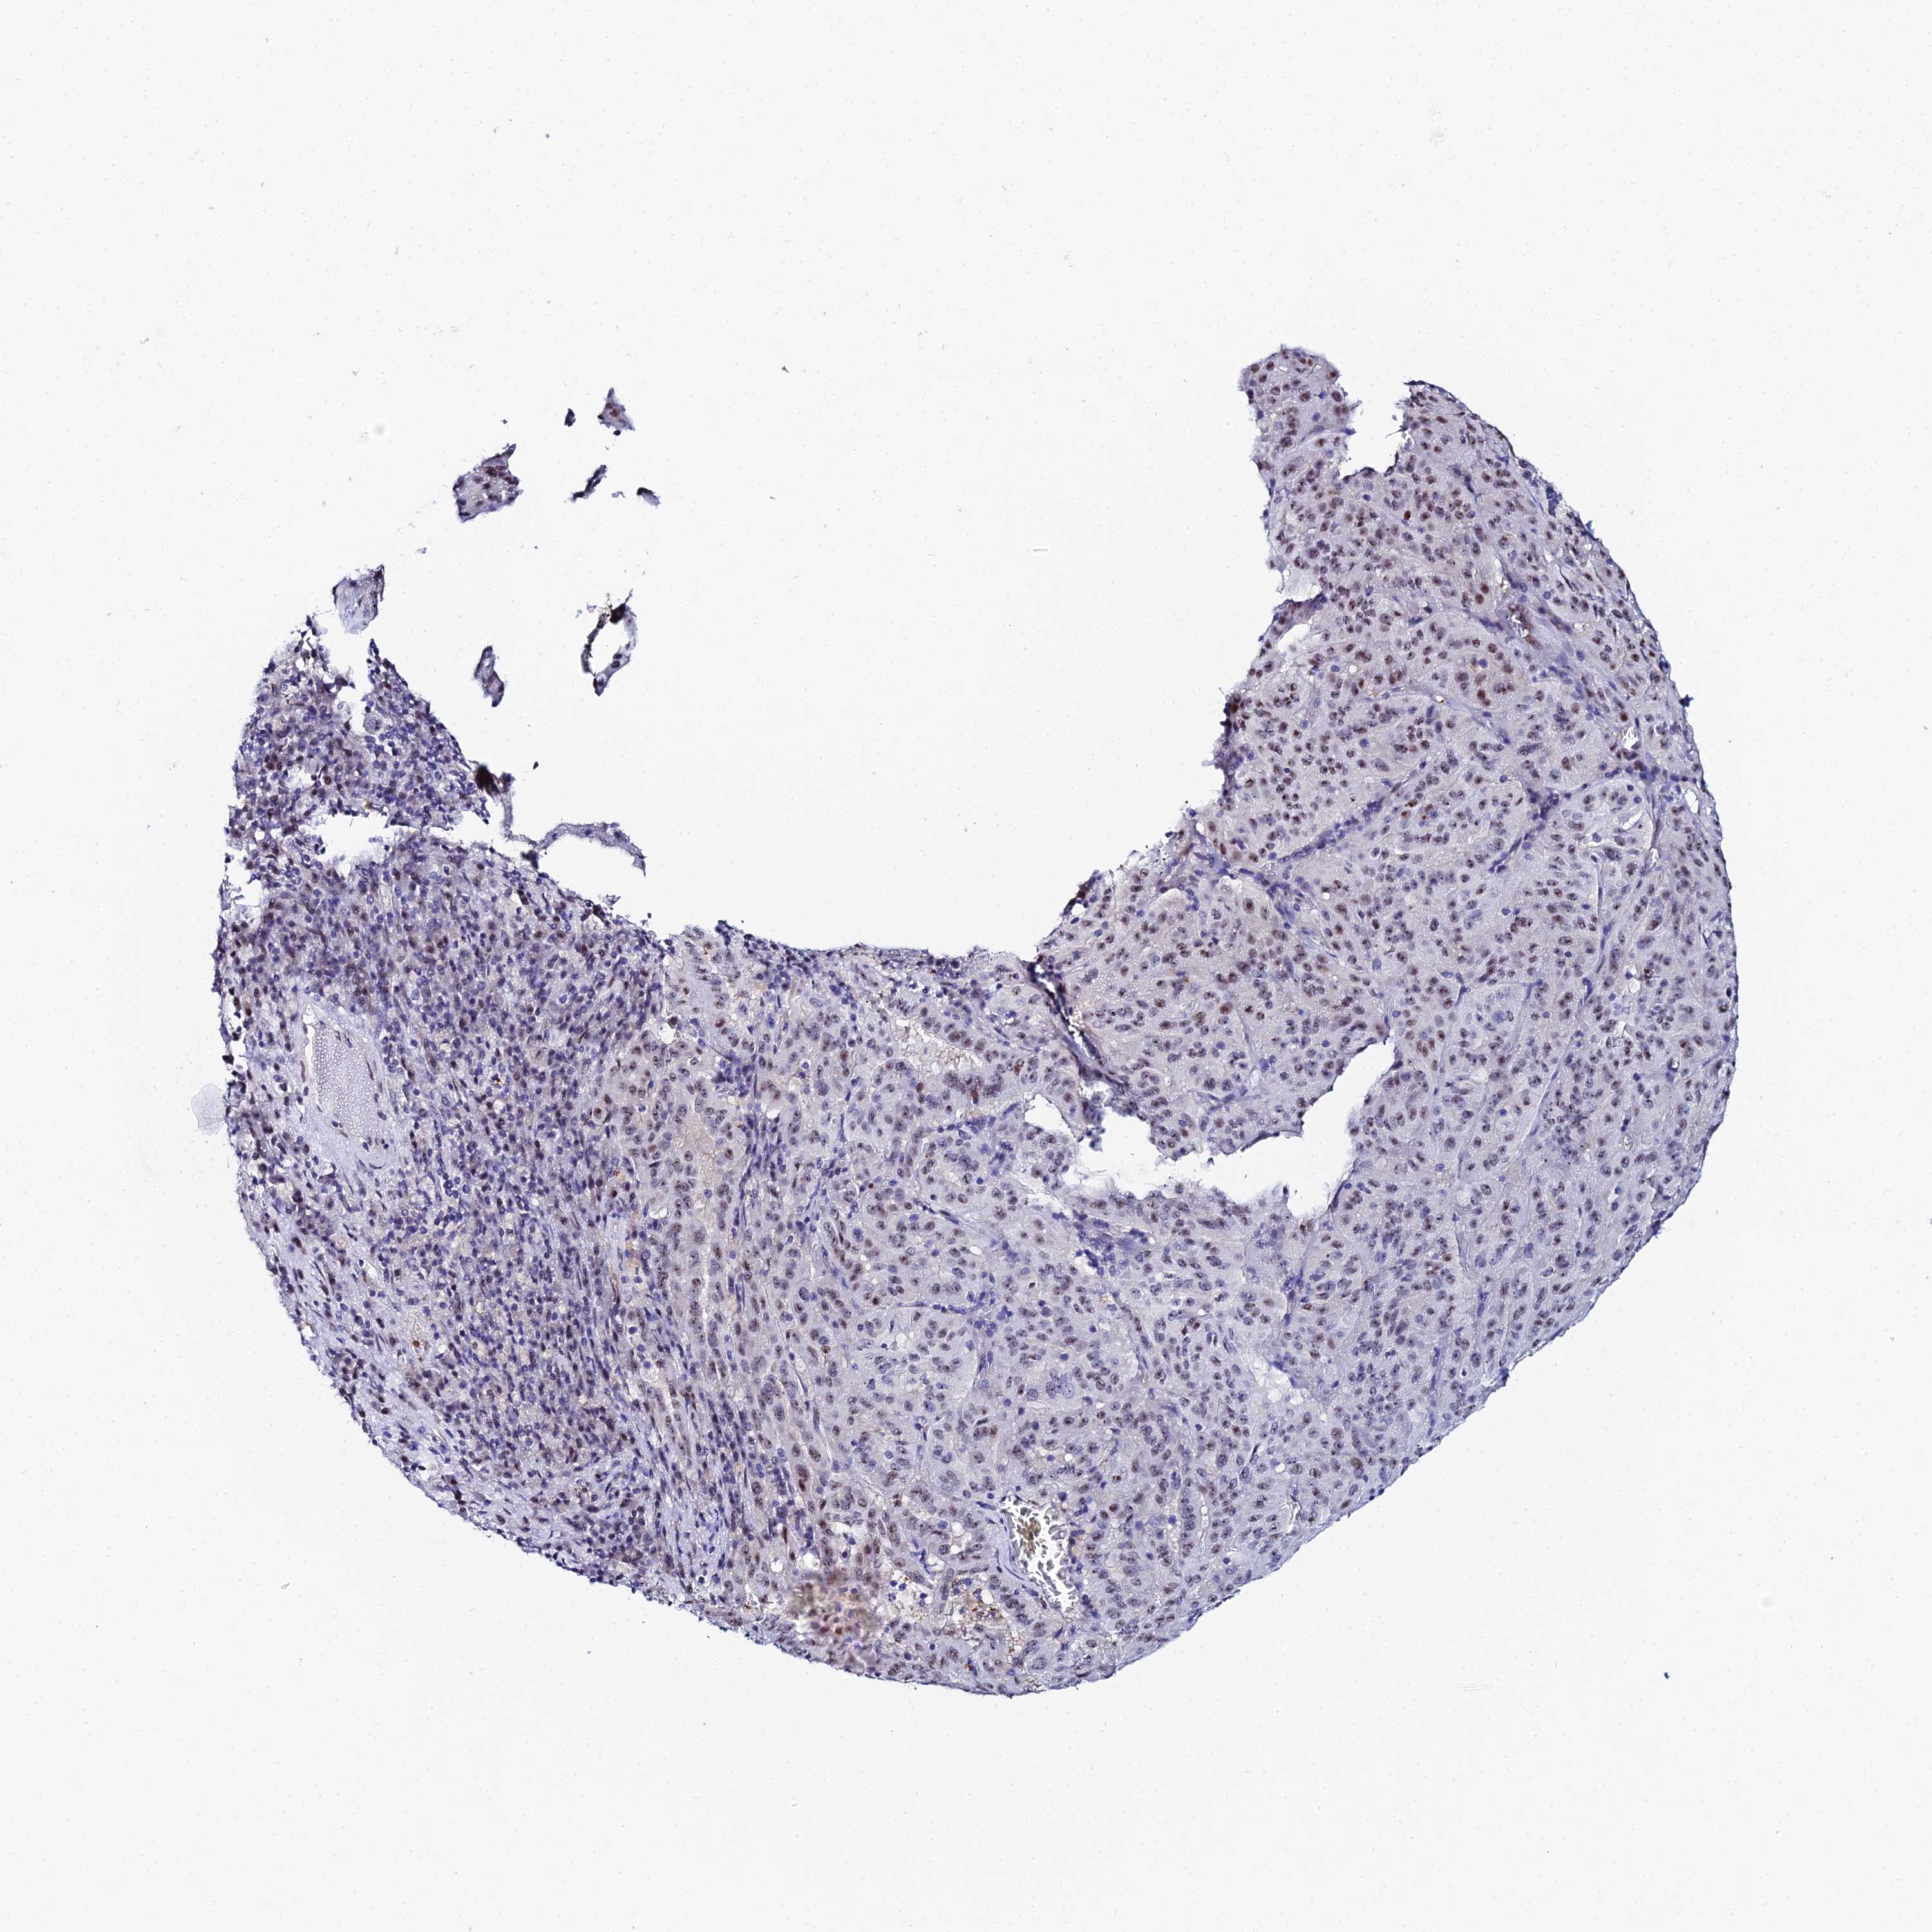

PANCREATIC CANCER - Protein expressioni

A mouse-over function shows sample information and annotation data. Click on an image to view it in a full screen mode. Samples can be filtered based on level of antibody staining by selecting one or several of the following categories: high, medium, low and not detected. The assay and annotation is described here.

Note that samples used for immunohistochemistry by the Human Protein Atlas do not correspond to samples in the TCGA dataset.

Antibody stainingi

Antibody staining in the annotated cell types in the current human tissue is reported as not detected, low, medium, or high, based on conventional immunohistochemistry profiling in selected tissues. This score is based on the combination of the staining intensity and fraction of stained cells.

Each image is clickable and will lead to virtual microscopy that enables deeper exploration of all samples and also displays staining intensity scores, fraction scores and subcellular localization as well as patient and tissue information for each sample.

Antibody HPA045889

Staining

High

Medium

Low

Not detected

Intensity

Strong

Moderate

Weak

Negative

Quantity

>75%

75%-25%

<25%

None

Location

Nuclear

Cytoplasmic/membranous

Cytoplasmic/membranous,nuclear

Adenocarcinoma, NOS